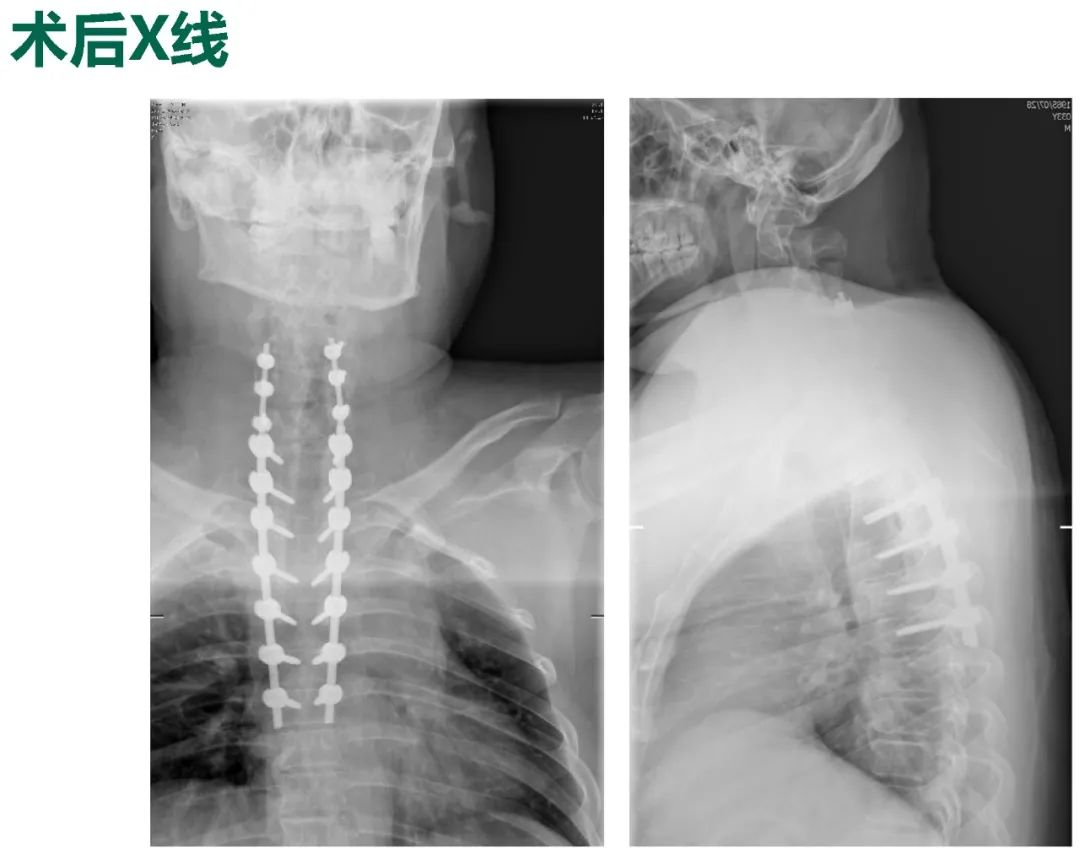

Thoracic spinal stenosis decompression(T2-T3)

术后3个月: